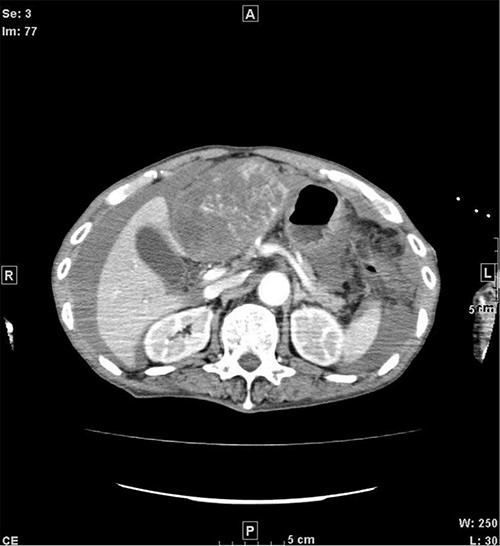

A 77-year-old man was referred to the Department of Gastroenterology at our hospital for suspicion of hepatocellular carcinoma and cancerous peritonitis. He was scheduled to be hospitalized for a thorough examination at a later date. However, 3 days after his first visit, he returned to the Emergency Department with a complaint of abdominal distension. He was hospitalized on the same day with a diagnosis of intra-abdominal bleeding due to a ruptured tumor in the lateral section of the liver. Computed tomography (CT) and magnetic resonance imaging (MRI) revealed a tumor with a maximum diameter of 8 cm in the lateral hepatic region and ascites around the liver and in the pelvic floor. Dynamic CT showed blood vessel-like early staining inside the tumor, and the contrast effect gradually enhanced (Fig. 1). During gadolinium ethoxybenzyl diethylenetriamine pentaacetic acid-enhanced MRI, this contrast effect gradually increased from the peripheral part toward the hepatocyte phase from the arterial phase (Fig. 2). Levels of tumor markers (alpha-fetoprotein, protein induced by vitamin K absence or antagonist-II, carcinoembryonic antigen and carbohydrate antigen 19–9) were within the normal range (Table 1). Based on the imaging findings, a diagnosis of spontaneously ruptured hepatic hemangioma was made. Since the patient’s general condition was stable and there were no findings suggestive of active bleeding, he decided to undergo elective surgery. Thus, he was not requested to continue being hospitalized and was discharged. Six days after discharge, he was transported to the emergency room in a state of shock and was hospitalized the same day. With the diagnosis of hemorrhagic shock due to re-rupture of the liver tumor (Fig. 3), emergency transarterial embolization (TAE) was performed. No apparent extravasation was observed on angiography, and A3 was embolized. Seven days later, he underwent left lateral hepatic segmentectomy. The postoperative course was generally good. The post-ruptured tumor was found in the left lateral segment, the cut surface was white, the edges were brown and the boundaries were unclear (Fig. 4). Histopathological examination revealed that sections of the white and brown parts of the margin were viable tumors, showing highly atypical spindle-shaped cells, arranged like sinusoidal vessels and partly solid, and there were many mitotic figures. There was no capsule, and the tumor infiltrated the surrounding liver parenchyma (Fig. 5a–c). Immunostaining showed CD31 (+), CD34 (partially positive), CK-CAM5.2 (−), α-SMA (−), HMB45 (indeterminate) and p53 (+), and the patient was diagnosed with hepatic angiosarcoma (Fig. 5d). Fever was observed 21 days after surgery, and CT was performed, revealing multiple masses in the liver (Fig. 6a). Another CT scan was performed 27 days postoperatively, which suggested that the liver masses were rapidly increasing; hepatic angiosarcoma recurrence was then confirmed (Fig. 6b). The patient requested the best supportive care at home and was discharged 31 days after the operation. He died at home 36 days after surgery.

CT at initial admission points out a tumor with a maximum diameter of 8 cm in the lateral hepatic region and ascites around the liver. Dynamic CT shows blood vessel-like early staining inside the tumor, and the contrast effect gradually enhances. (a) Arterial phase, (b) equilibrium phase. CT, computed tomography.